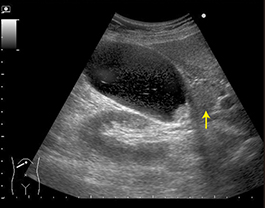

右季肋部痛を伴う胆嚢腫大は急性胆嚢炎の所見だが、総胆管結石の発作との判別が問題となる。本例のように胆管拡張がなく胆嚢頸部の嵌頓結石(矢印)が描出できれば、鑑別は可能である。 |